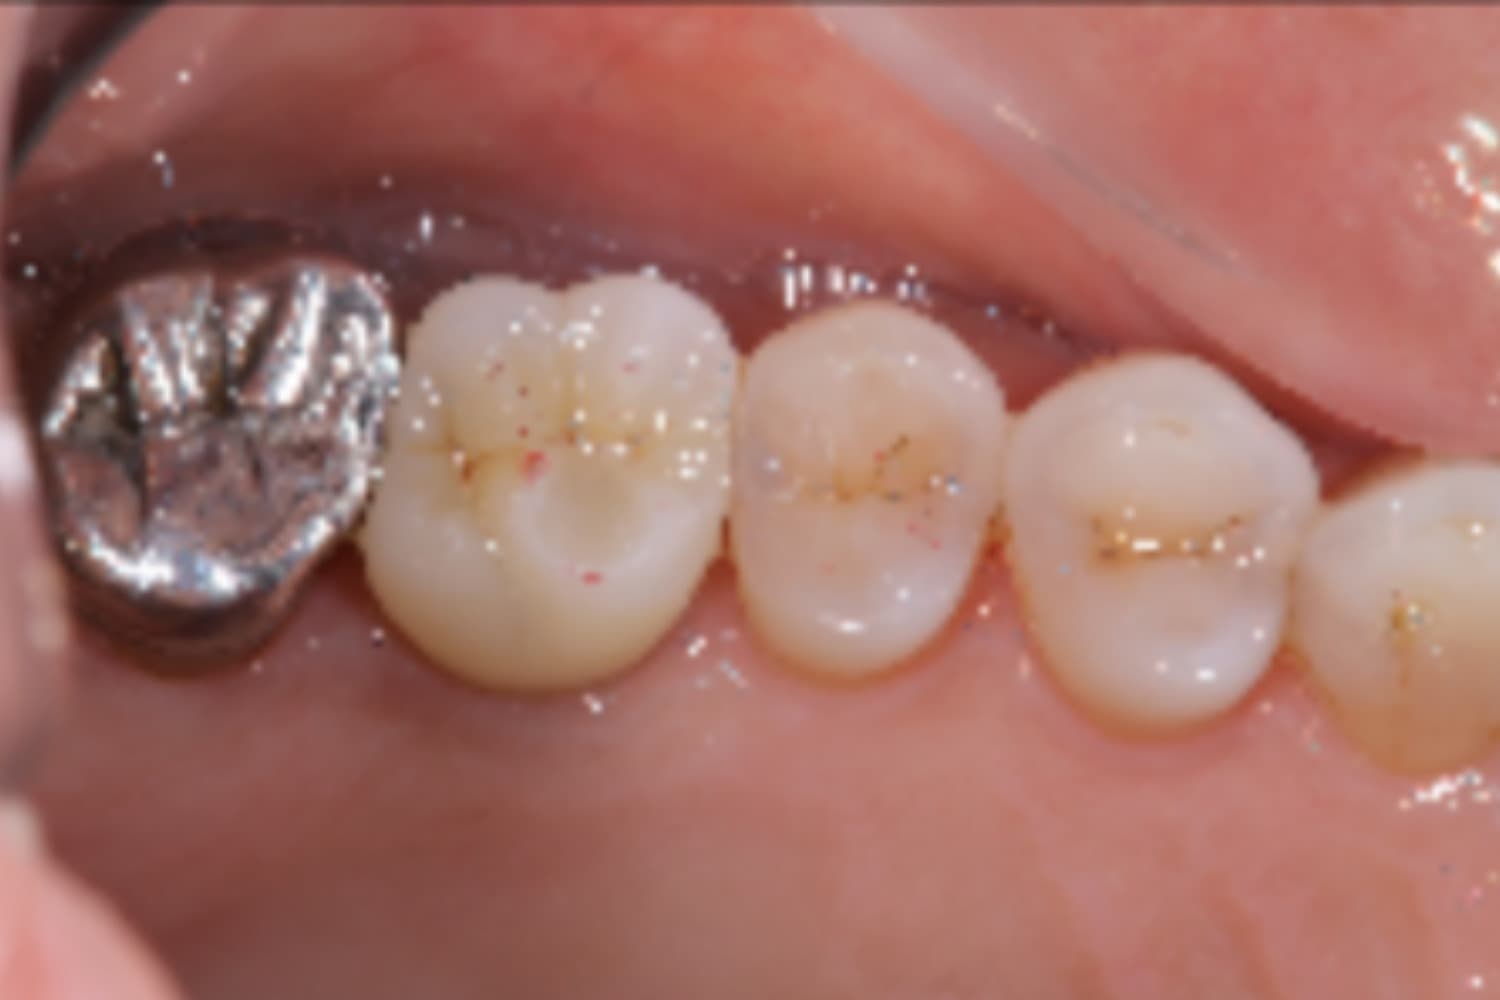

右上欠損部のインプラント治療

After

右上欠損部にインプラント治療を行なった

治療期間

4カ月

治療回数

10回

費用

434,500円

副作用・リスク

・感染やインプラントの結合不良の可能性がある